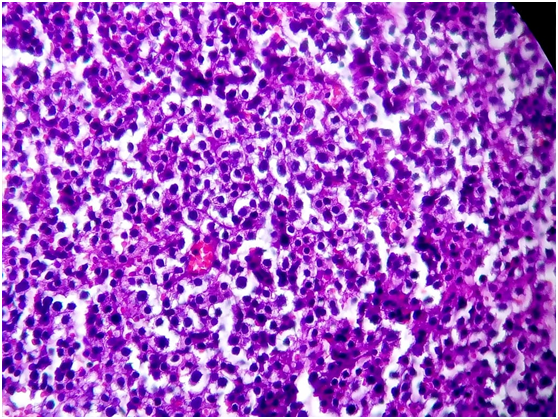

A biopsy is performed for the retro-auricular lymphadenopathy, and finally histopathological and immunohistochemical examination confirmed the diagnostic of nodular sclerosing Hodgkin's disease stage IV (Ann Arbor staging) (Figure 2). The tumor’s cells were expressing CD15, CD30 (Figure 3 & 4). The patient is then transferred to the hematology department for therapeutic management.

Figure 2 HES staining - High magnification: Presence of numerous Reed Sternberg cells